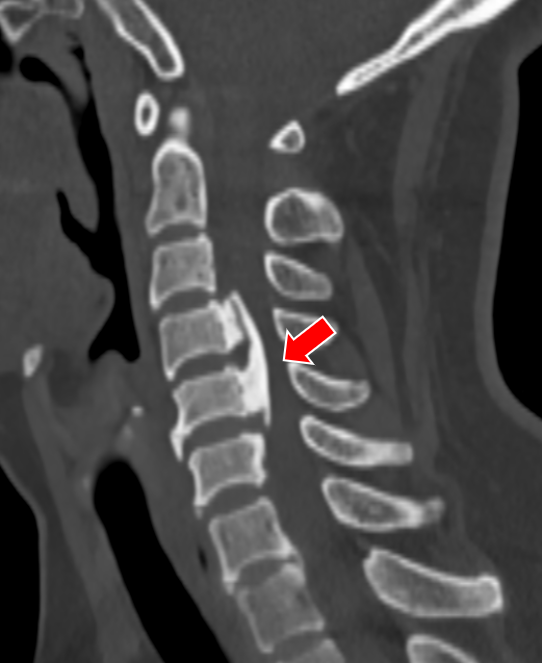

(颈椎CT提示患者C5-6的椎间盘突出棒骨性狭窄)

(颈椎CT提示患者C4-5的椎间盘突出(右后方),椎间隙后缘骨赘增生)